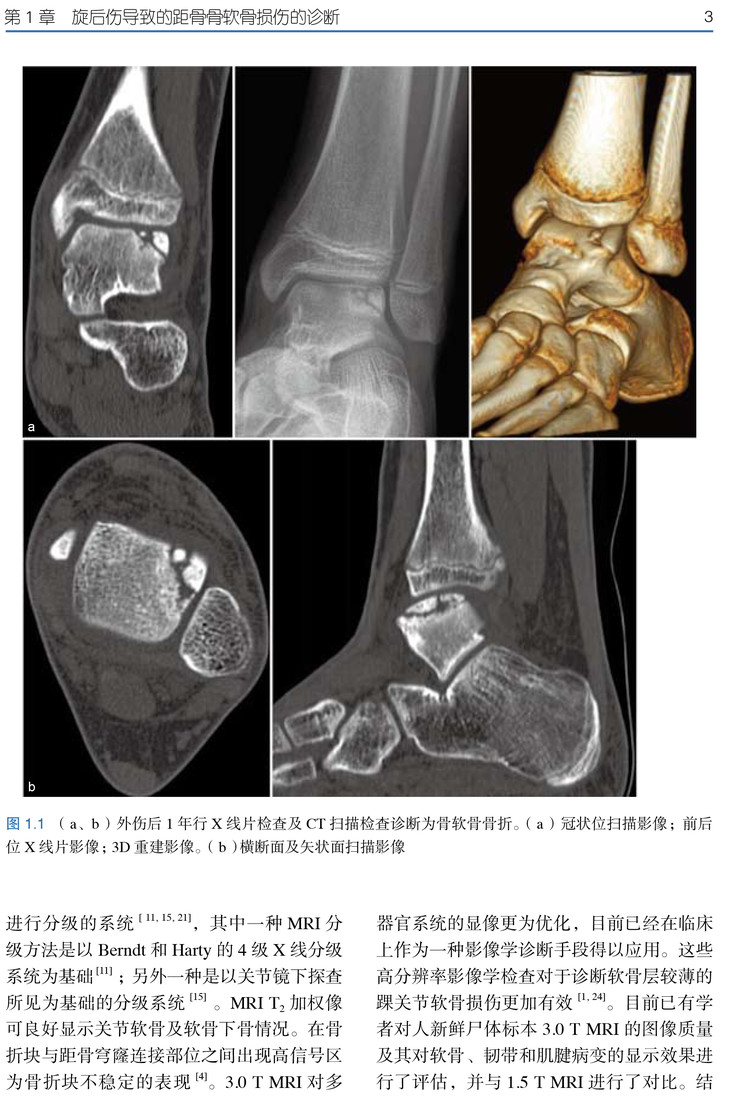

★ 内页插图 ★